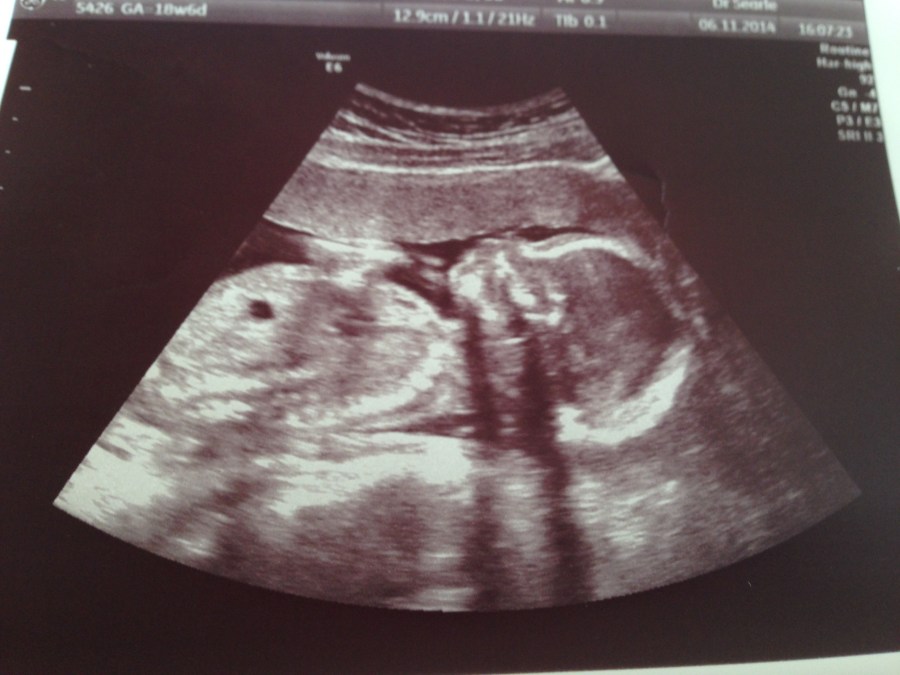

And there he was. There you were, my Sam. Quietly listening to your father’s voice. Watching me carefully when they placed you next to me. Desperately trying to free your little swaddled arms (something you do to this day) so you could take in more of the world. And then, finally, blissfully suckling away with an unmatched life force. But that was always you. You always wanted to be here. Exactly a year ago, I was lying in a room in a local fertility clinic as they put my son back in me. Defying crazy odds, he had survived four days in an incubator environment, becoming a few cells then a few dozen more, then a zygote. Then he made a home in my body, grew still into an embryo, then a foetus. And now here he is.